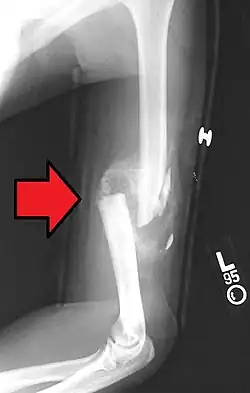

A displaced supracondylar fracture in a child